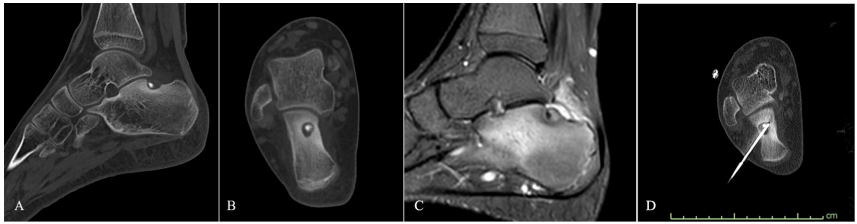

本综述系统探讨了CT引导射频热消融术(CT-RFTA)治疗非典型部位骨样骨瘤(OO)的技术策略与临床价值。作者结合六例罕见部位(指骨、骨骺旁、髋臼内、跟骨、椎体及桡骨)病例,详细阐述了针对毗邻生长板、关节软骨及神经血管结构的保护性技术(如钻孔路径优化、生理盐水隔离灌注等),证实了该技术在复杂解剖区域应用的安全性及有效性(症状完全缓解率100%,无严重并发症),为临床处理特殊类型OO提供了重要参考。